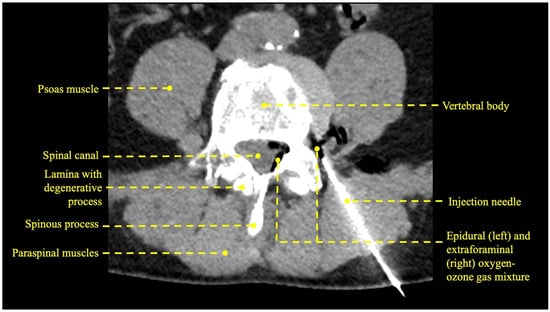

- Muto, M.; Andreula, C.; Leonardi, M. Treatment of herniated lumbar disc by intradiscal and intraforaminal oxygen-ozone (O2-O3) injection. J. Neuroradiol. 2004, 31, 183–189. [Google Scholar] [CrossRef] [PubMed]

- Giurazza, F.; Guarnieri, G.; Murphy, K.J.; Muto, M. Intradiscal O2O3: Rationale, Injection Technique, Short- and Long-term Outcomes for the Treatment of Low Back Pain Due to Disc Herniation. Can. Assoc. Radiol. J. 2017, 68, 171–177. [Google Scholar] [CrossRef]